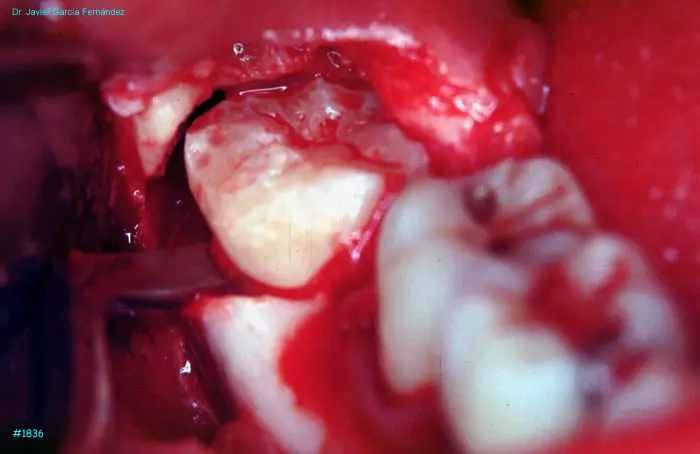

image 102